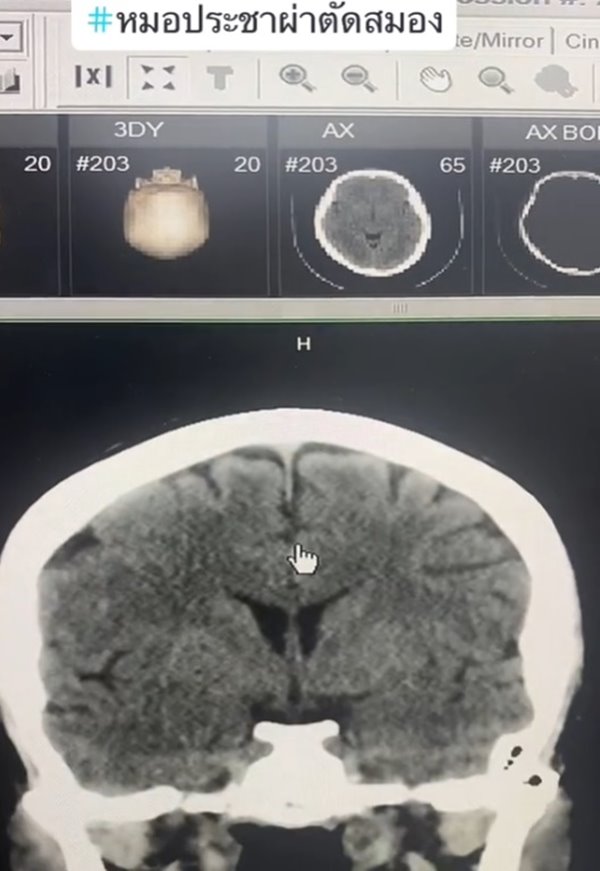

เปิดภาพเทียบให้ดูชัด ๆ สมองคนทั่วไปกับคนติดเหล้า เห็นภาพซีทีสแกนชัดเจน พบคนกินเหล้าจะมีอาการสมองฝ่อ ล้มนิดเดียวเลือดออกในสมอง ต่างกับคนทั่วไปชัดเจน ใครกินเหล้าต้องคิดให้ดี

เราอาจจะรู้กันว่า การติดเหล้านั้นมีผลทำให้เป็นโรคตับแข็ง และเป็นปัจจัยที่ทำให้เกิดโรคร้ายต่าง ๆ ตามมาได้มาก แต่ในความเป็นจริงแล้ว การดื่มเหล้าและมีอาการติดเหล้า ก็ส่งผลต่อสมองได้เช่นกัน และล่าสุดก็มีภาพซีทีสแกนมายืนยันในเรื่องนี้แล้ว

วันที่ 30 กรกฎาคม 2566 TikTok @doctor.pracha_neuro_surg ของ นพ.ประชา กัญญาประสิทธิ์ ประสาทศัลยแพทย์ มีการเล่าเรื่องราวประสบการณ์การผ่าตัดสมอง พร้อมข้อเตือนใจประชาชน โดยเปรียบเทียบกันระหว่าง สมองคนทั่วไปกับสมองคนที่ติดเหล้า มันต่างกันอย่างไรบ้าง คลิปนี้มีคนดูมากกว่า 1 ล้านครั้ง

หมอประชายังเล่าเพิ่มเติมว่า คนที่ดื่มเหล้าบ่อย ๆ เวลาล้มหัวกระแทก จะทำให้เลือดออกได้ง่าย เพราะเนื้อที่สมองน้อย ผลกระทบอื่น ๆ ก็ยังมีโอกาสเป็นเบาหวาน ไขมัน โอกาสอัมพาตจากสโตรก ดังนั้น มีโอกาสเสียชีวิตหรือพิการมากกว่าคนทั่วไป